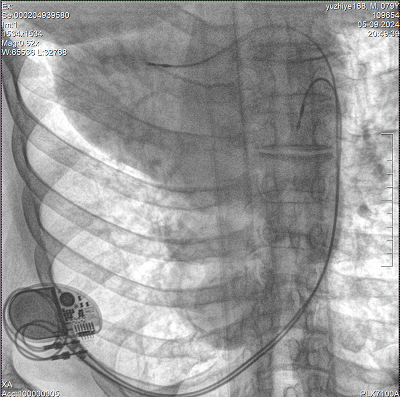

具備血管造影及數(shù)字減影(DSA)、路徑圖(Road-map)、透視、攝影等功能。 廣泛適用于介入科、血管外科、腫瘤科、消化內(nèi)科及骨科等多個臨床科室,典型應(yīng)用包括:TACE(肝腫瘤栓塞與化療灌注術(shù))、心臟起搏器置入術(shù)、四肢動脈造影術(shù)、下肢靜脈濾器置入術(shù)、ERCP(經(jīng)內(nèi)鏡逆行胰膽管造影術(shù))等。

設(shè)備搭載自主研發(fā)的大功率高壓發(fā)生器、高熱容球管與大尺寸平板探測器,配合先進(jìn)圖像處理算法及高效冷卻循環(huán)系統(tǒng),能夠在長時間手術(shù)過程中持續(xù)輸出高清圖像并保持幀率穩(wěn)定。

預(yù)留高壓注射器聯(lián)動接口,C形臂開始透視時,高壓注射器自動注入造影劑,提高術(shù)中造影減影效率,減少醫(yī)師手推造影劑所受到的輻射暴露劑量。